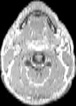

Visible Human male: Sectio transversalis 1216

CT

NMR

Pd T1 T2